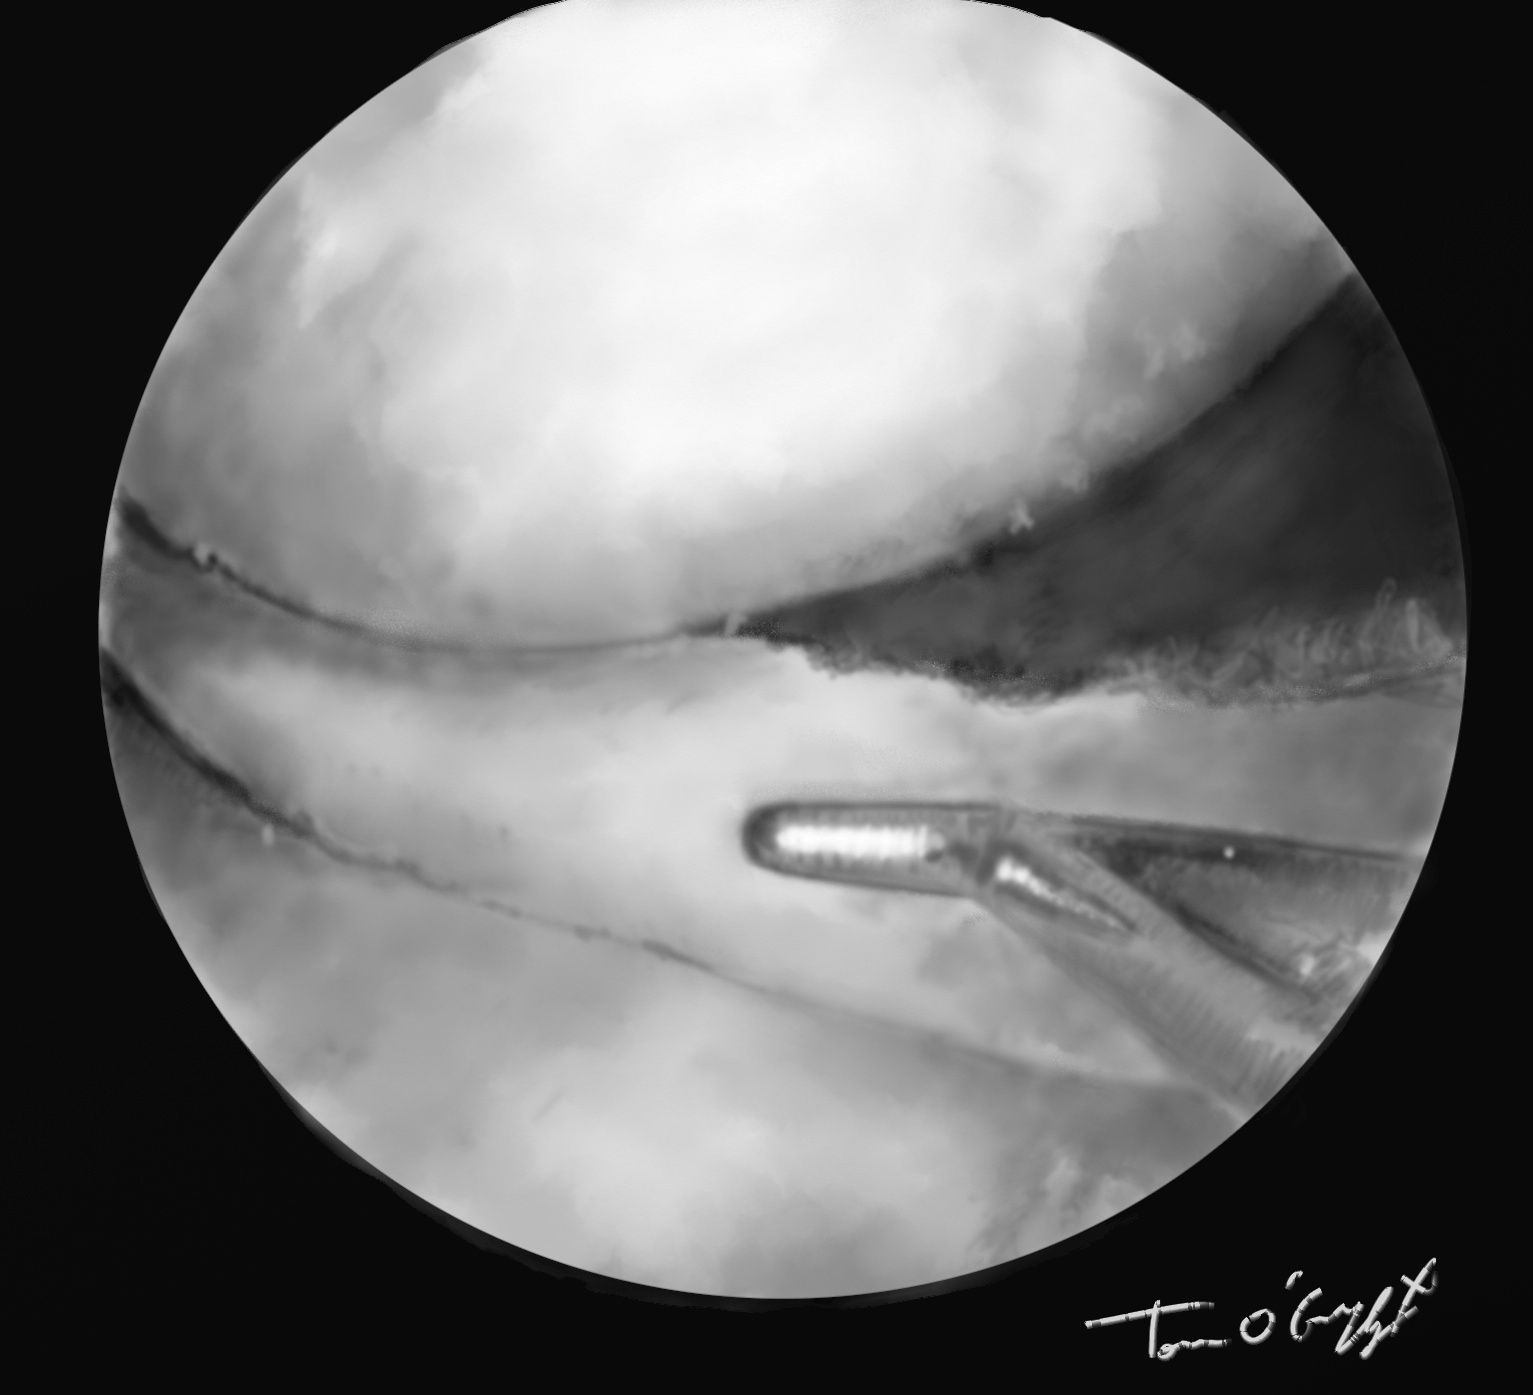

genou arthroscopie menisque suture

arthroscopie suture d’une fissure méniscale longitudinale

L’arthroscopie visualise alors exactement la déchirure méniscale, permet de réduire une luxation en anse de seau, de découper et régulariser une déchirure en languette, de suturer une fissure longitudinale ou en cas de désinsertion périphérique. En sachant que les atteintes externes ont une bonne chance de cicatrisation donc suture, et internes quasiment aucune donc exérèse.